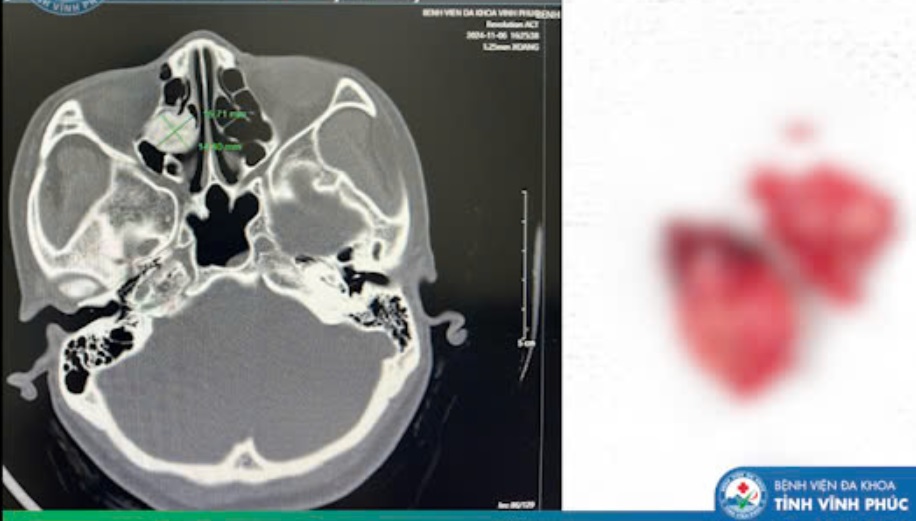

Người bệnh N.T.L.A (43 tuổi, ở Tam Dương - Vĩnh Phúc), có triệu chứng đau âm ỉ nửa đầu bên phải kéo dài, các triệu chứng này không thuyên giảm dù đã sử dụng thuốc điều trị bệnh lý thần kinh và xoang. Người bệnh đã được thăm khám chuyên khoa Tai Mũi Họng, thực hiện các xét nghiệm, chụp CT Scanner mũi xoang có hình ảnh u xương xoang sàng bên phải, kích thước khoảng 1.6x1.5cm.

Sau khi hội chẩn chuyên khoa và loại trừ các nguyên nhân khác, bác sĩ xác định đây là u xương lành tính trong xoang sàng và quyết định phẫu thuật nội soi là phương pháp điều trị tối ưu cho người bệnh.